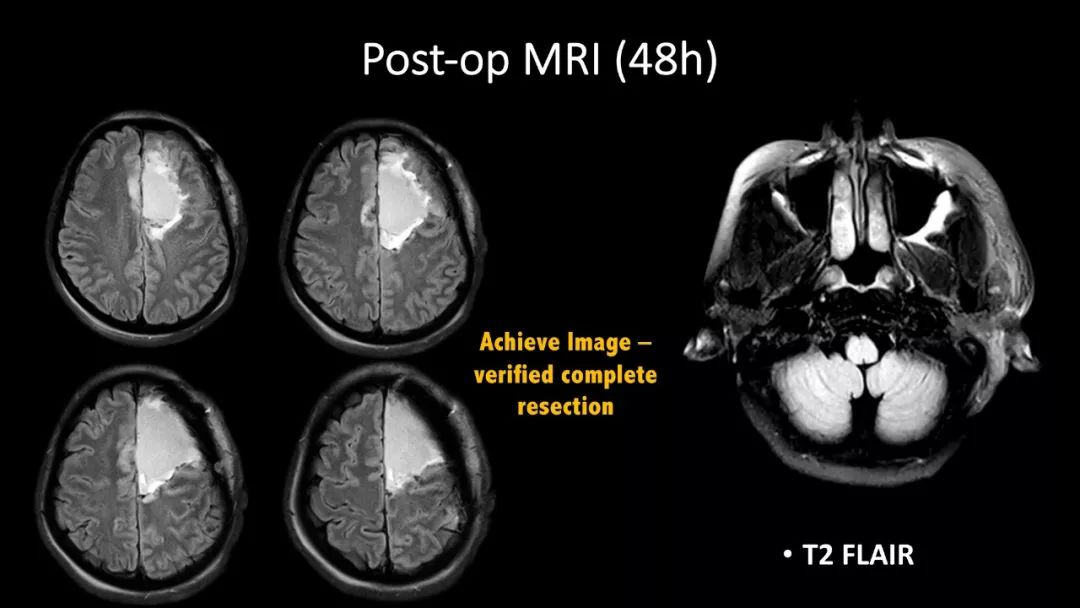

神外资讯将定期分享第一届“凝神聚胶”全国青年医师胶质瘤临床病例分析大赛的获奖病例。本期分享的病例是“二等奖”获得者——福建医科大学附属第一医院吴赞艺医师带来的:“Recurrent Anaplastic Oligodendroglioma Case Sharing(复发间变性少突胶质细胞瘤病例分享)”,欢迎观看、分享。